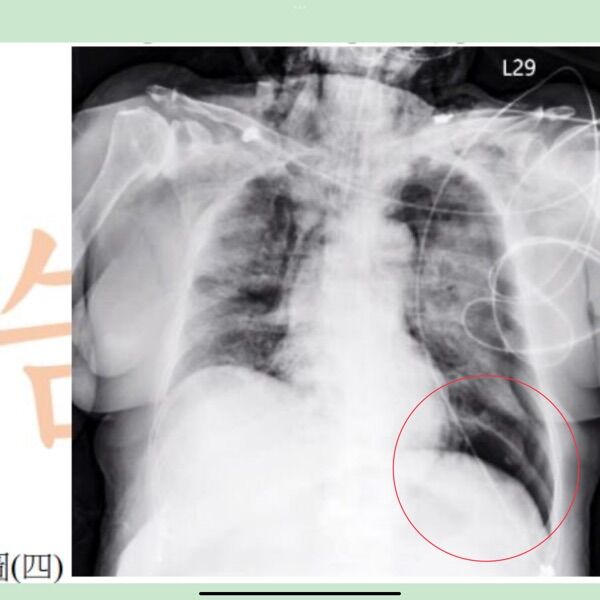

36. 76 歲病人曾因呼吸衰竭插上氣管內管並使用呼吸器輔助,呼吸器設定參數為 FiO2 100 %、 Pressure20cmH2O及PEEP10cmH2O;今日病人突然呼吸喘促,呼吸40次/分、心跳 125次/分、血壓 90 / 60 mmHg 、血氧飽和度 SpO288 %、皮膚濕冷及胸部X光檢查結果如圖 (四 ) 。下列後續處置何者最適當?(PEEP:positive end - expiratory pressure )

可以發現CXR左下葉有出現明顯界線,且影像顯示較黑,疑似有氣胸,因此,需放置胸管,改善氧合。